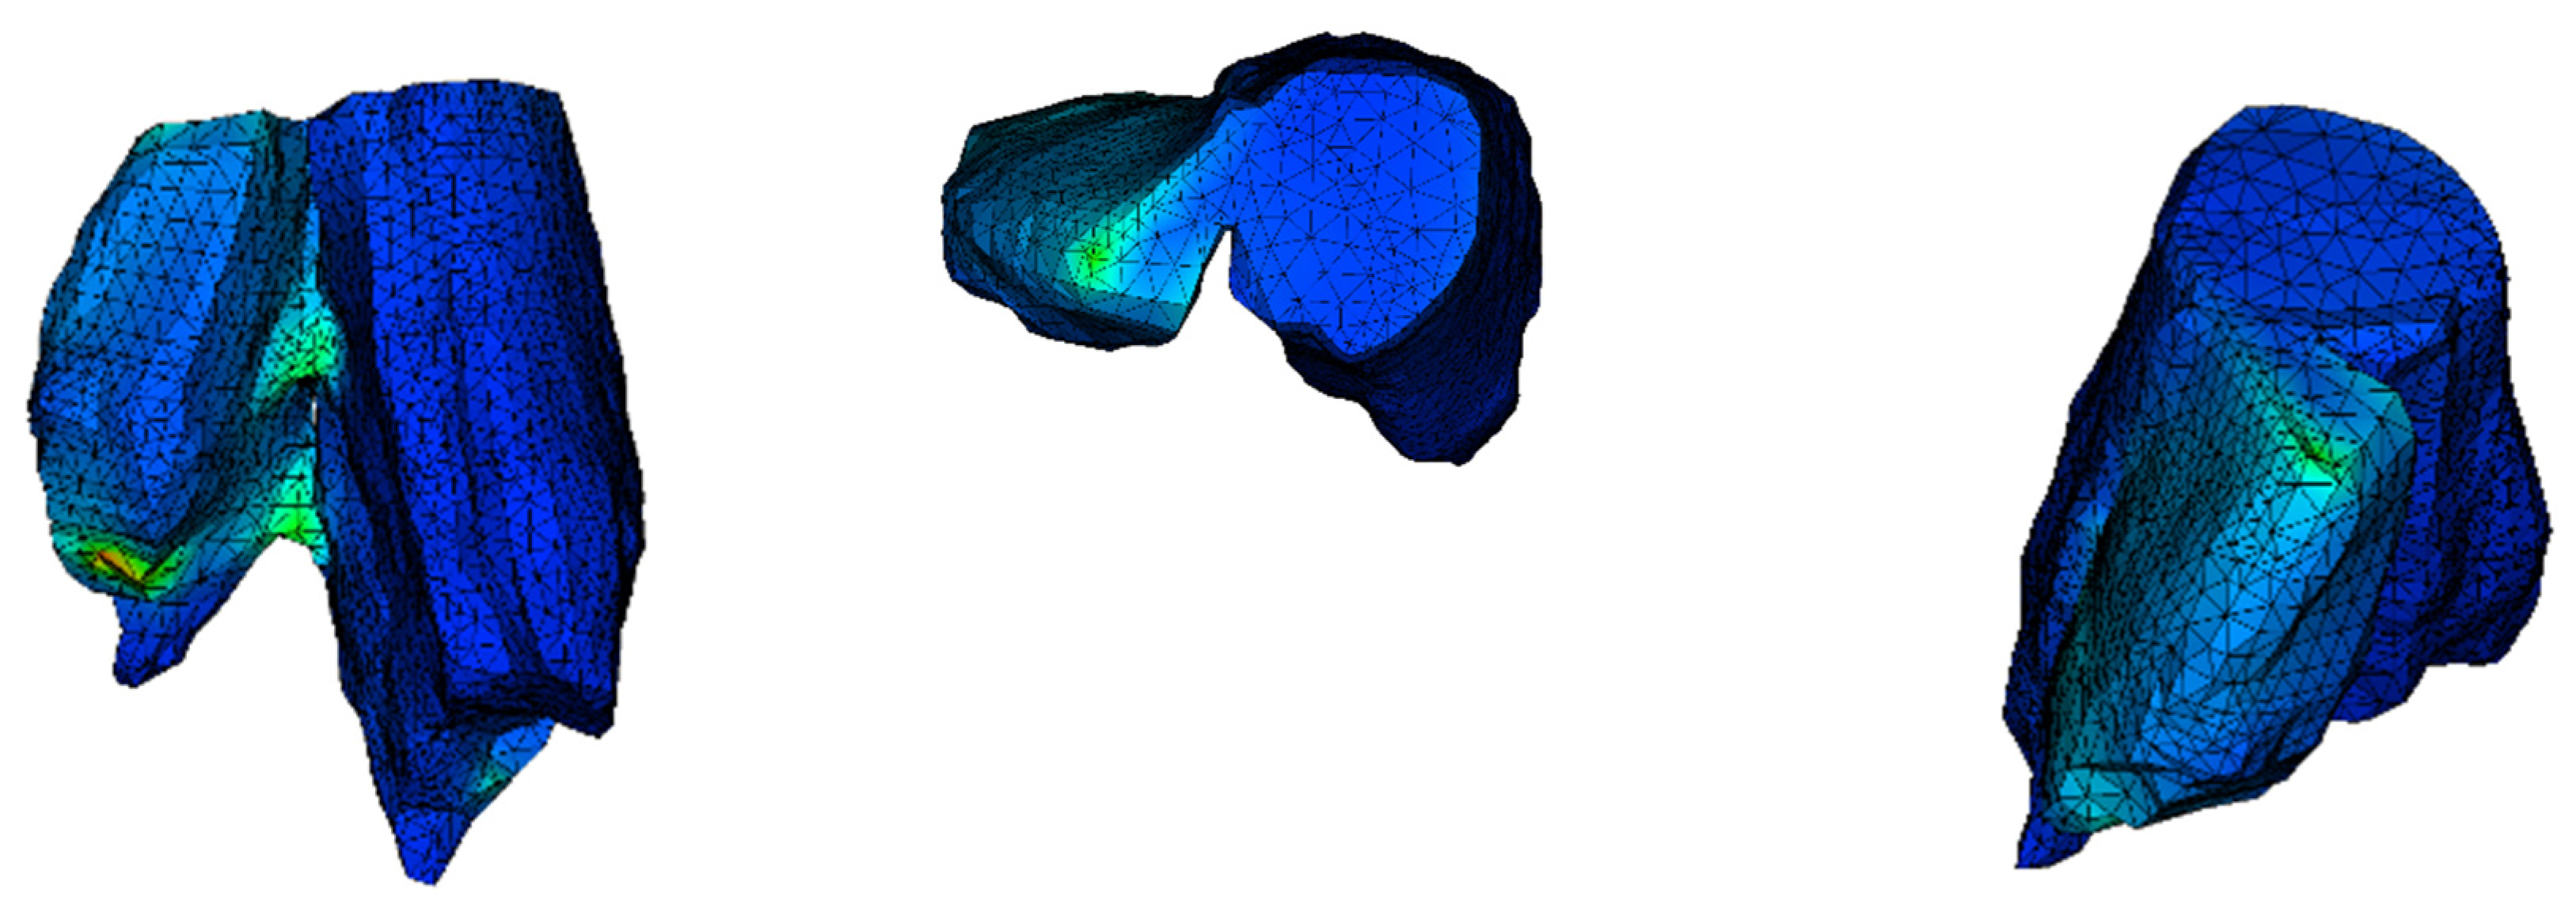

3.4. Analysis of the PCL Scaffold

Stress distribution appears to be different from the previous two simulations. The display tool is changed to stress on node instead of stress on element. Additionally, as the mesh was quite fine in this analysis, it is not shown. The simulation of the scaffold follows the exact geometry of the implant as defined in Rhino software. The intent is to visualize the stress distribution in the scaffold model in order to improve its design. A simplified approach could be followed by applying the homogenized approach. Stress can be transferred from the broken part to the other one through the scaffold (Figure 8). The maximum stress is greater than the strength of the scaffold (Table 3). According to these analysis results, a PCL scaffold could not be a treatment solution for a fracture like this, although it could possibly have a beneficial impact if it was combined with screws. The core function of a scaffold like this is the acceleration of cell growth.

Figure 8. Maximum von Mises stress in MPa.